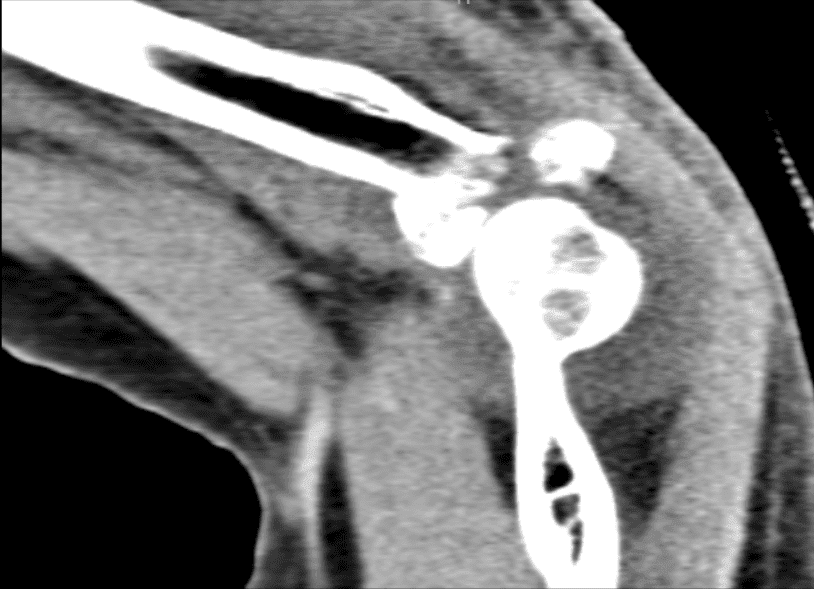

The patient presented a CT-scan result that showed Comminuted displaced acute fracture of the radial head as described above. Essentially nondisplaced acute fracture of the coronoid process of the ulna. Hemarthrosis.

CT Left Elbow Non-contrast